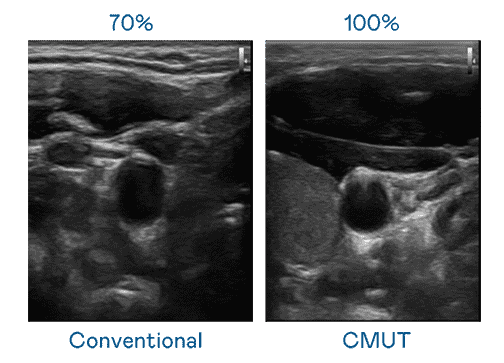

CMUT 技术是一种用电容式微机电元件来产生超音波讯号的技术。。。与传统 PZT 压电式技术相比,,CMUT 频宽增加 30%,,,,更宽频的超音波讯号让影像解析度大幅提升,,,,是实现高影像品质医疗超音波扫描、、促进精准医疗发展的关键技术。。。

大频宽带来超清晰影像

超音波影像的解析度高低,,,首先取决于探头能发出的讯号频宽。。z6尊龙 CMUT 可提供高清晰的超音波讯号,,提供高频宽、、、高灵敏度、、、影像纹理细节更高的超音波影像,,,,协助医护人员缩短影像判读时间及利用精准的医疗影像进行诊断。。